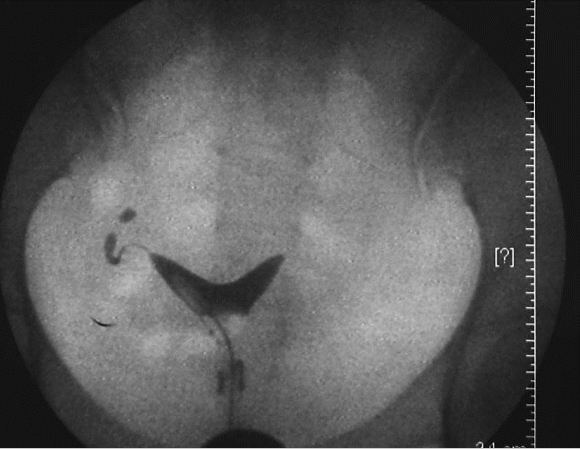

图22-1 处女膜闭锁并阴道、宫腔积血

绝大多数患者至青春期发生周期性下腹坠痛,进行性加剧。严重者可引起肛门胀痛和尿频等症状。检查可见处女膜膨出,表面呈紫蓝色;肛诊可扣及盆腔囊性包块。偶有幼女因大量黏液潴留在阴道内,导致处女膜向外凸出、下腹坠痛而就诊。盆腔超声检查可见阴道内有积液。确诊后应及时手术治疗。先用粗针穿刺处女膜中部膨隆部,抽出陈日积血后再进行“X”形切开,排出积血;常规检查宫颈是否正常,切除多余的处女膜,修剪处女膜,再用可吸收缝线缝合切口边缘。